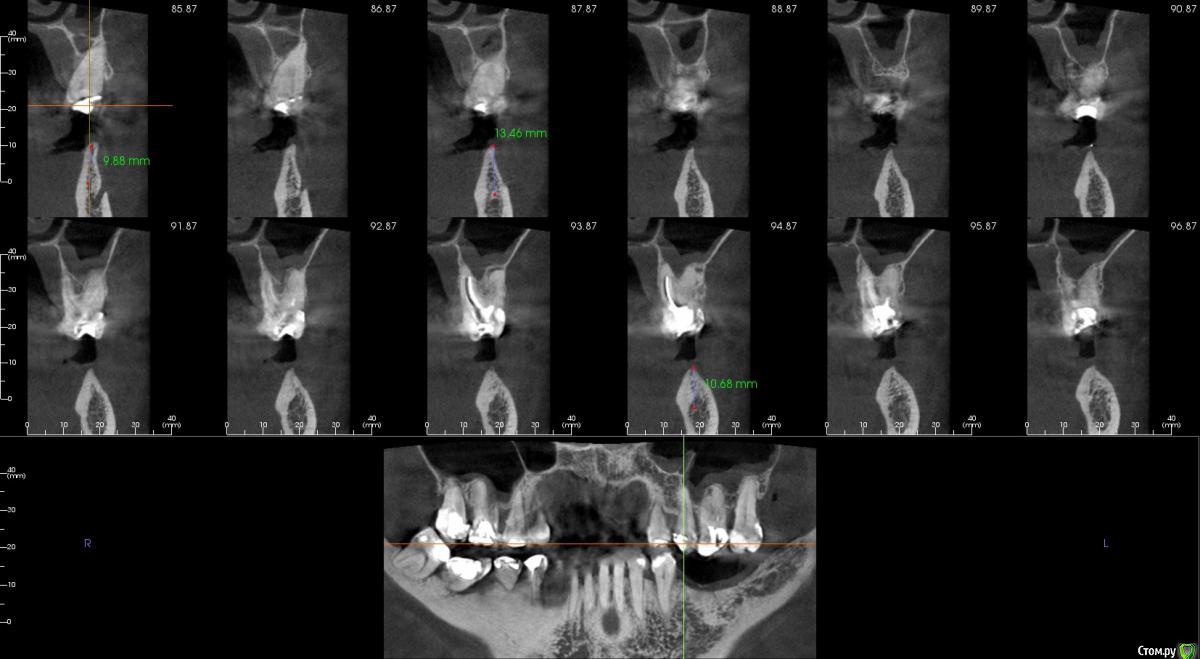

kamranchick Опубликовано 23 августа, 2016 Поделиться Опубликовано 23 августа, 2016 Господа, как посоветуете поступить на 4 сегменте?Какая методика здесь будет предсказуема, и возможно ли установка сразу болтов, так как пациентка уезжает на 8 месяцев в командировку, смущает что менталис рядом и очень тоненький биотип десны Ссылка на комментарий

kamranchick Опубликовано 24 августа, 2016 Автор Поделиться Опубликовано 24 августа, 2016 А зачем Вам пятый?! Ставьте 6, 7 и консоль с 6 внутренний.. Добро, тогда 4.0 на 8.5 должны встать как родные Ссылка на комментарий